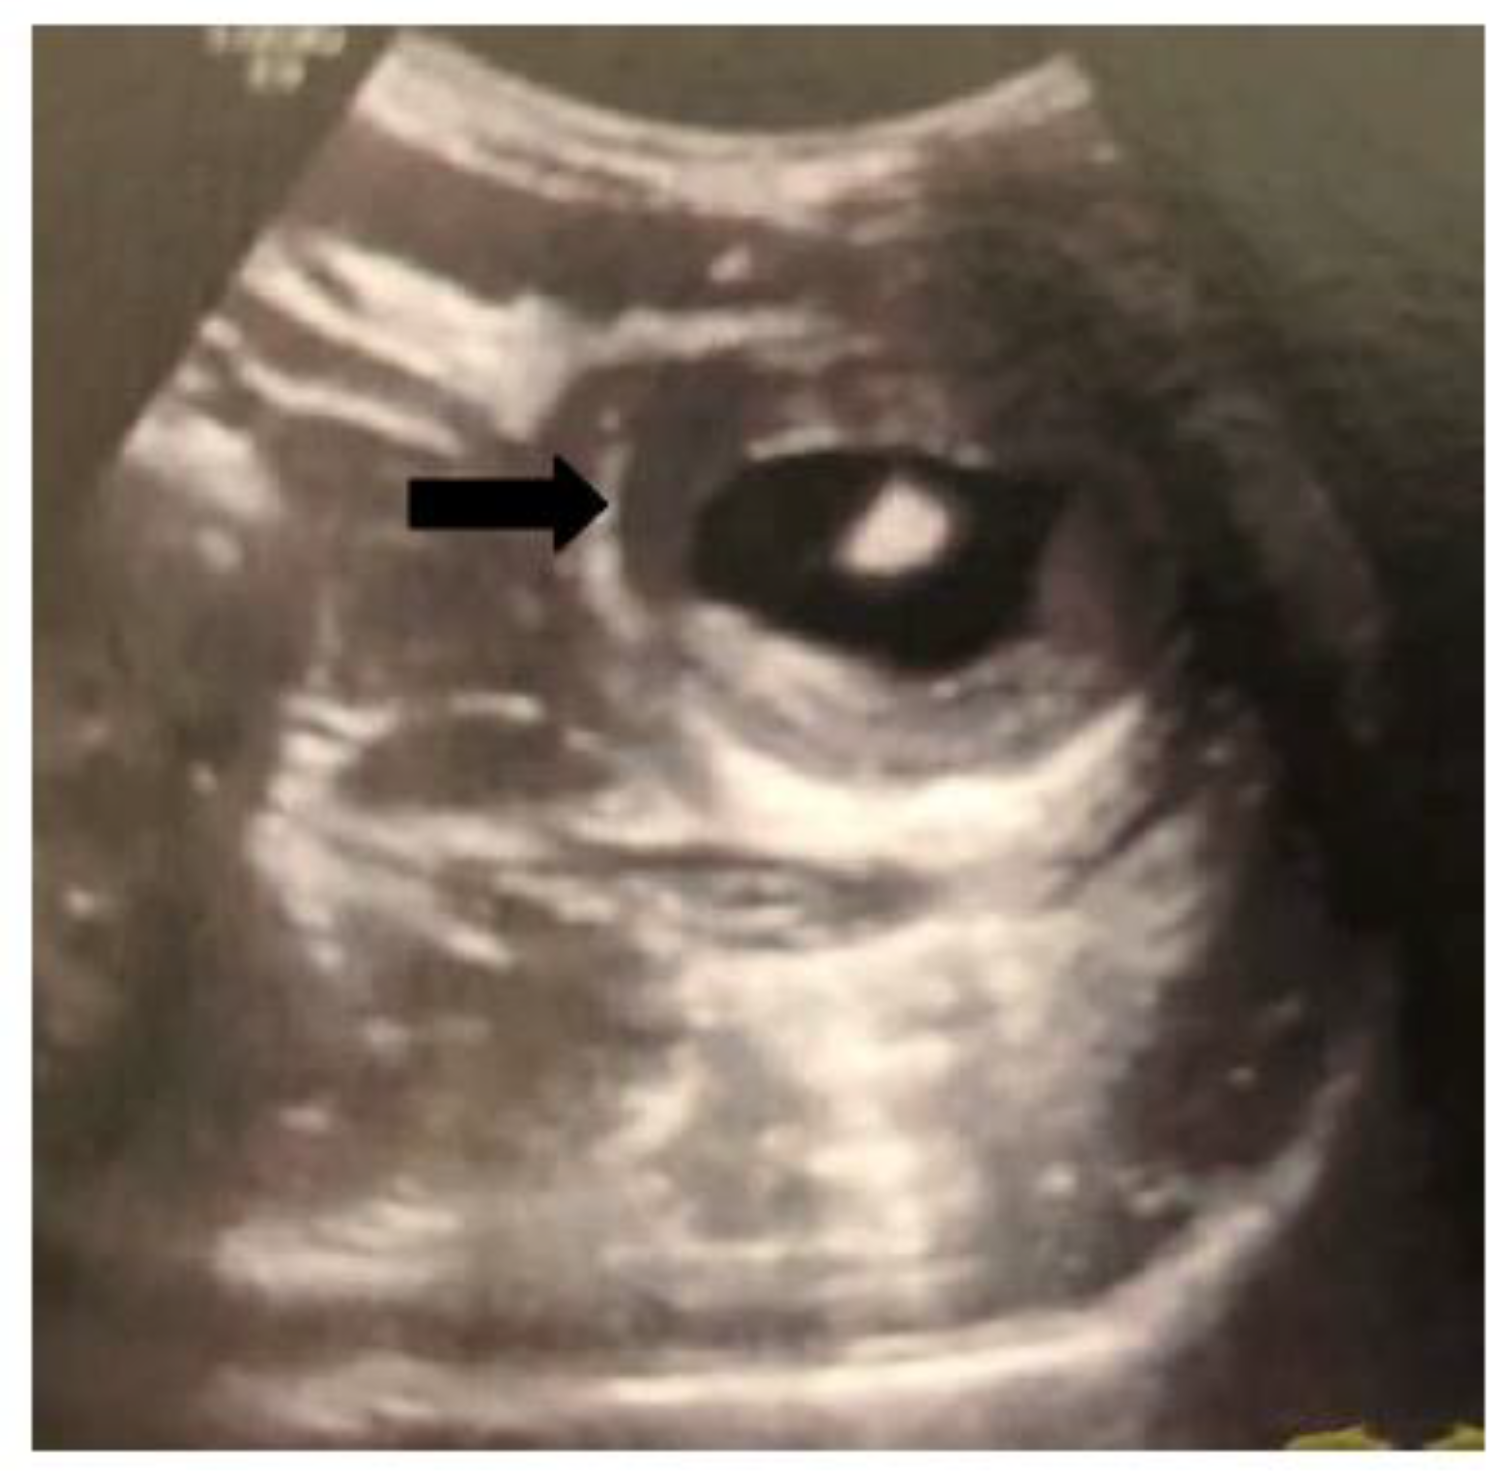

The second case concerned a 38-year-old female patient with a free medical history, who presented in the emergency department with progressive recurrent epigastric pain, vomiting and diarrhea over the last ten days. Physical examination revealed tenderness and a palpable mass in the upper abdomen. All laboratory inflammation markers were within the normal range (WBC: 8.8 mm3/μL, CRP: 0,0 mg/dL). At first, an ultrasound examination was performed and the diagnosis of a bowel intussusception was suspected through demonstration of a typical "target sign" (Figure 2).

Ultrasound is a noninvasive, non-radiation method, therefore is considered the imaging modality of choice for diagnosing intussusception in children but may be pathognomonic also in adult patients. The typical "target or bull's eye sign” that is created from the intussuscepted loops that are forming an external ring around the intussusceptum may be depicted by an experienced radiologist [17] (Figure 2). In pediatric patients the reported sensitivity of the method is almost 100%, but in adults patients it is much lower (30-60%) [6,7,18]. However, according to Wang et al. if a palpable mass is present, the diagnostic accuracy of the method is much higher and may reach 91% [7]. From the four cases that we present ultrasound was performed in two patients with epigastric pain to exclude a gallbladder pathology and was diagnostic only in the second case that presented also with a palpable mass. Regarding CT scan, it seems to be the most useful diagnostic tool in adult intussusception, with a reported diagnostic accuracy ranging from 78% up to 100% [6,7,12,18,19]. The intussusception is depicted as an inhomogeneous mass lesion with a central area of fat with enhanced vascularization (intussuscepted mesentery) and multiple, eccentric layers that represent the thickened segments of bowel (intussusceptum and intussuscipiens) [20]. Furthermore, CT may provide indirect information in cases of a malign disease (metastatic lesions in the liver, lymphadenopathy) but most of the times is not capable to depict the primary neoplasm that causes the intussusception.

Figure 2. Ultrasound examination of the patient (second case) on admission. The typical "target sign" (black arrow) is clearly demonstrated raising the suspicion of a bowel intussusception.